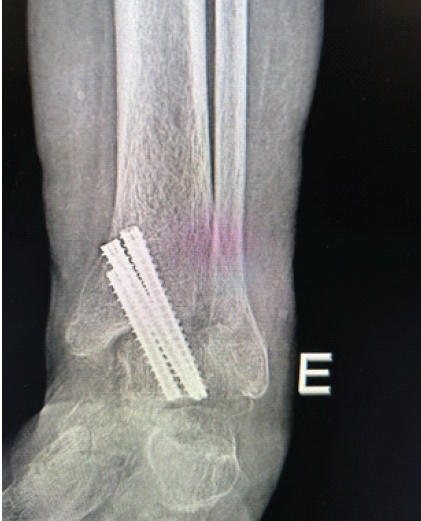

Clinical and Functional Outcome of Distal Tibial Fractures Treated with Minimally Invasive Percutaneous Plate Osteosynthesis Technique using Anatomical Distal Tibial Plate: A Case Series

H Rohit Karthik , Venkata Kiran Pillella , Hemanth Raj , Madhukar Chegu , Vijay Narasimman Reddy , G Puguzhendhi